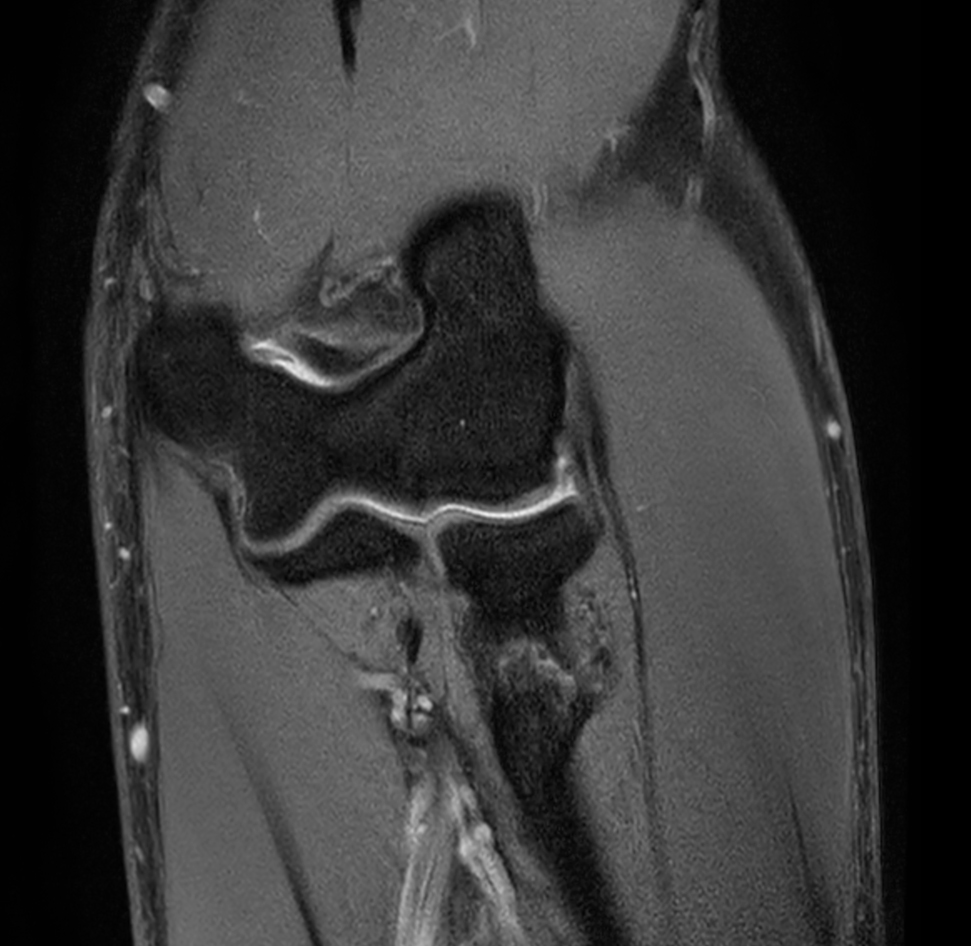

Axial T2w TSE